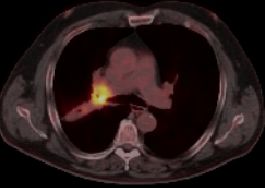

blauer Punkt   56-jähriger Mann mit einem Adeno-Ca des rechten Mittellappens. Im CT große Raumforderung im rechten Hilus. Das PET-CT zeigt, dass der eigentliche Tumor unterhalb der Raumforderung sitzt.